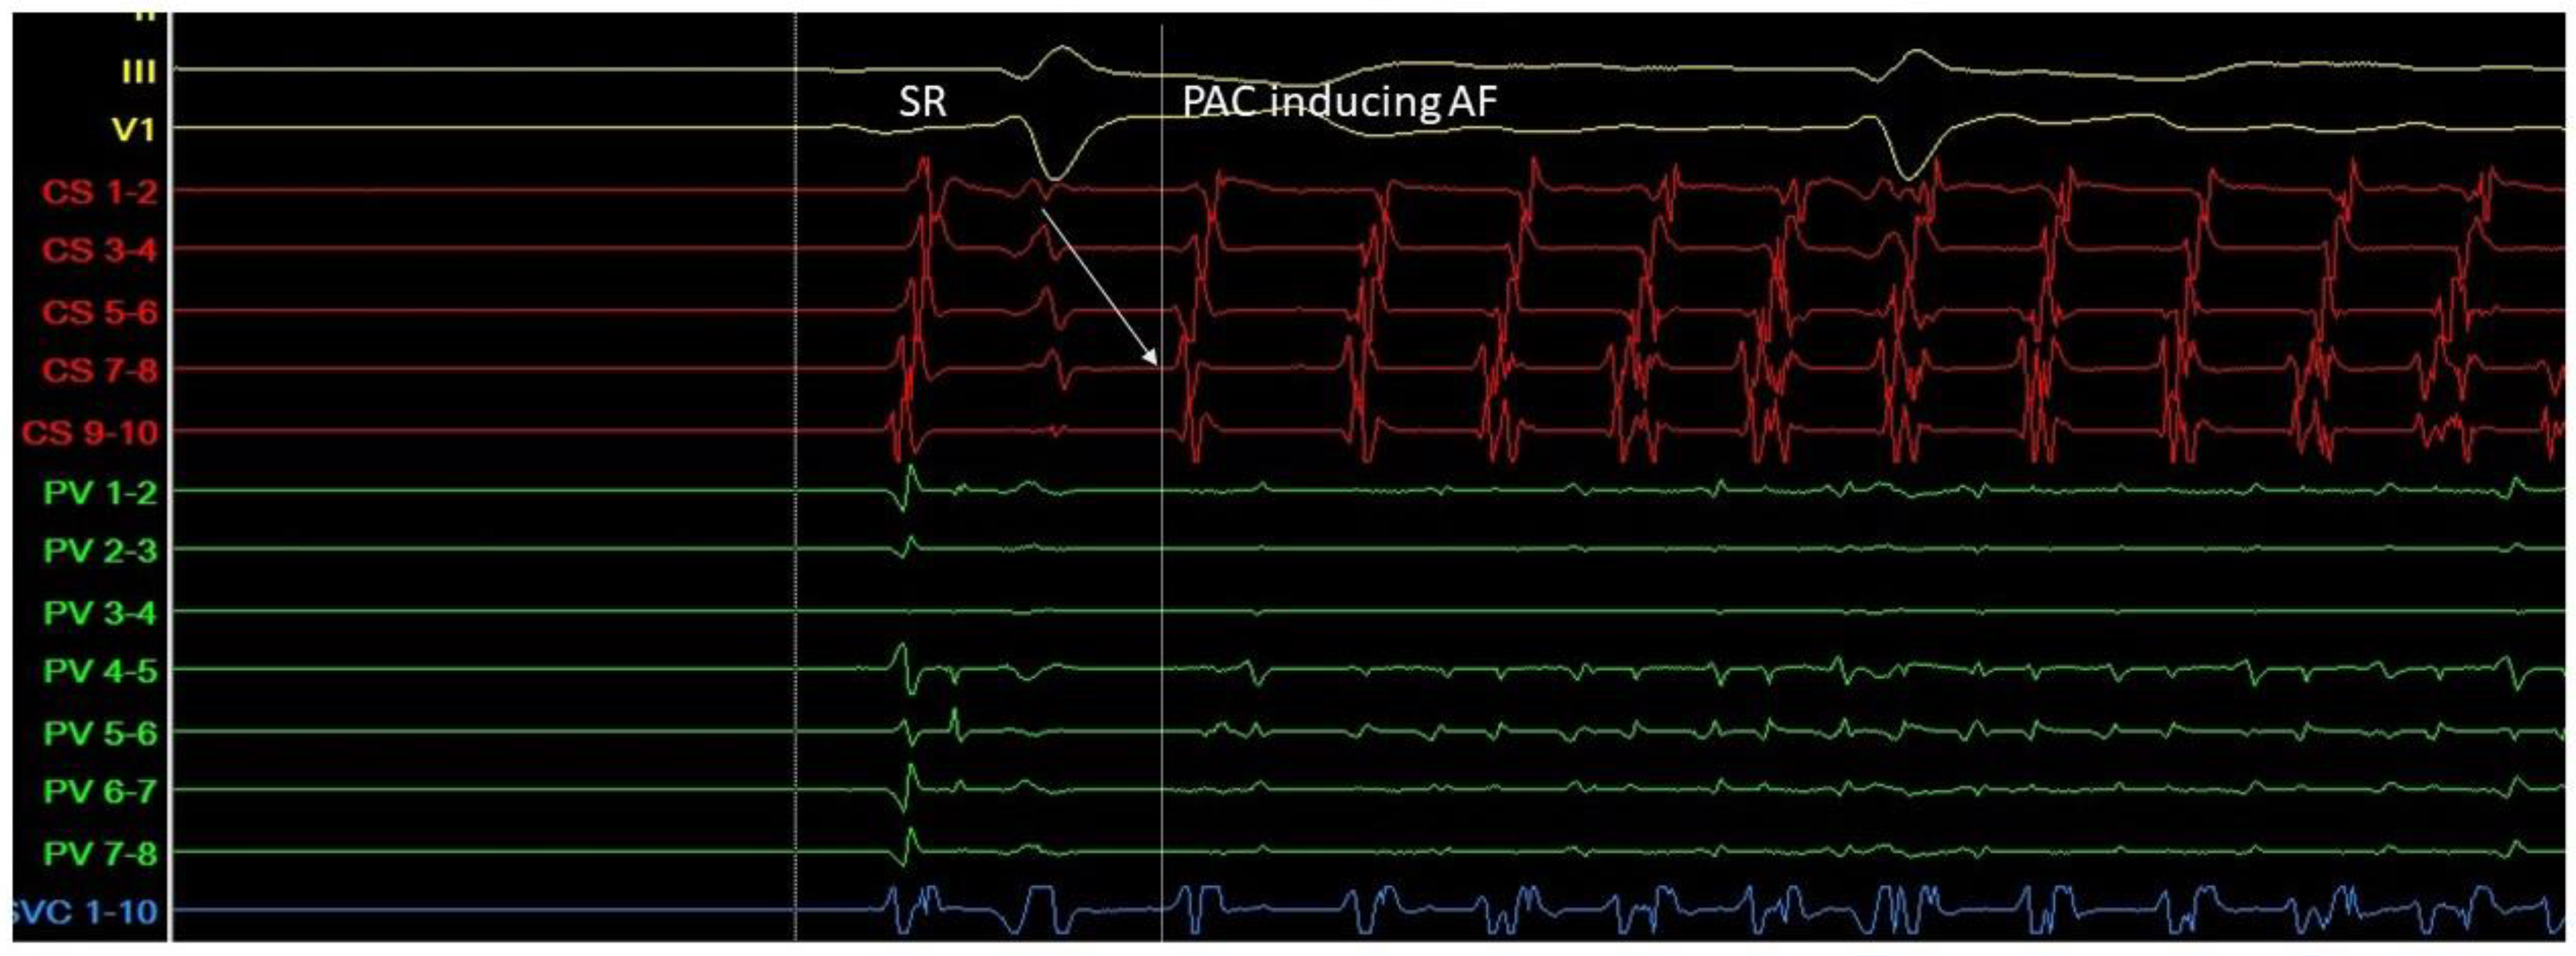

Figure 3.

A. Atrial ectopic beat originates from the proximal aspect of the coronary sinus (arrow at the CS 7-8 electrogram)—a non PV trigger—and induces atrial fibrillation (G. Leventopoulos’ archive). PV: pulmonary vein. CS: coronary sinus.